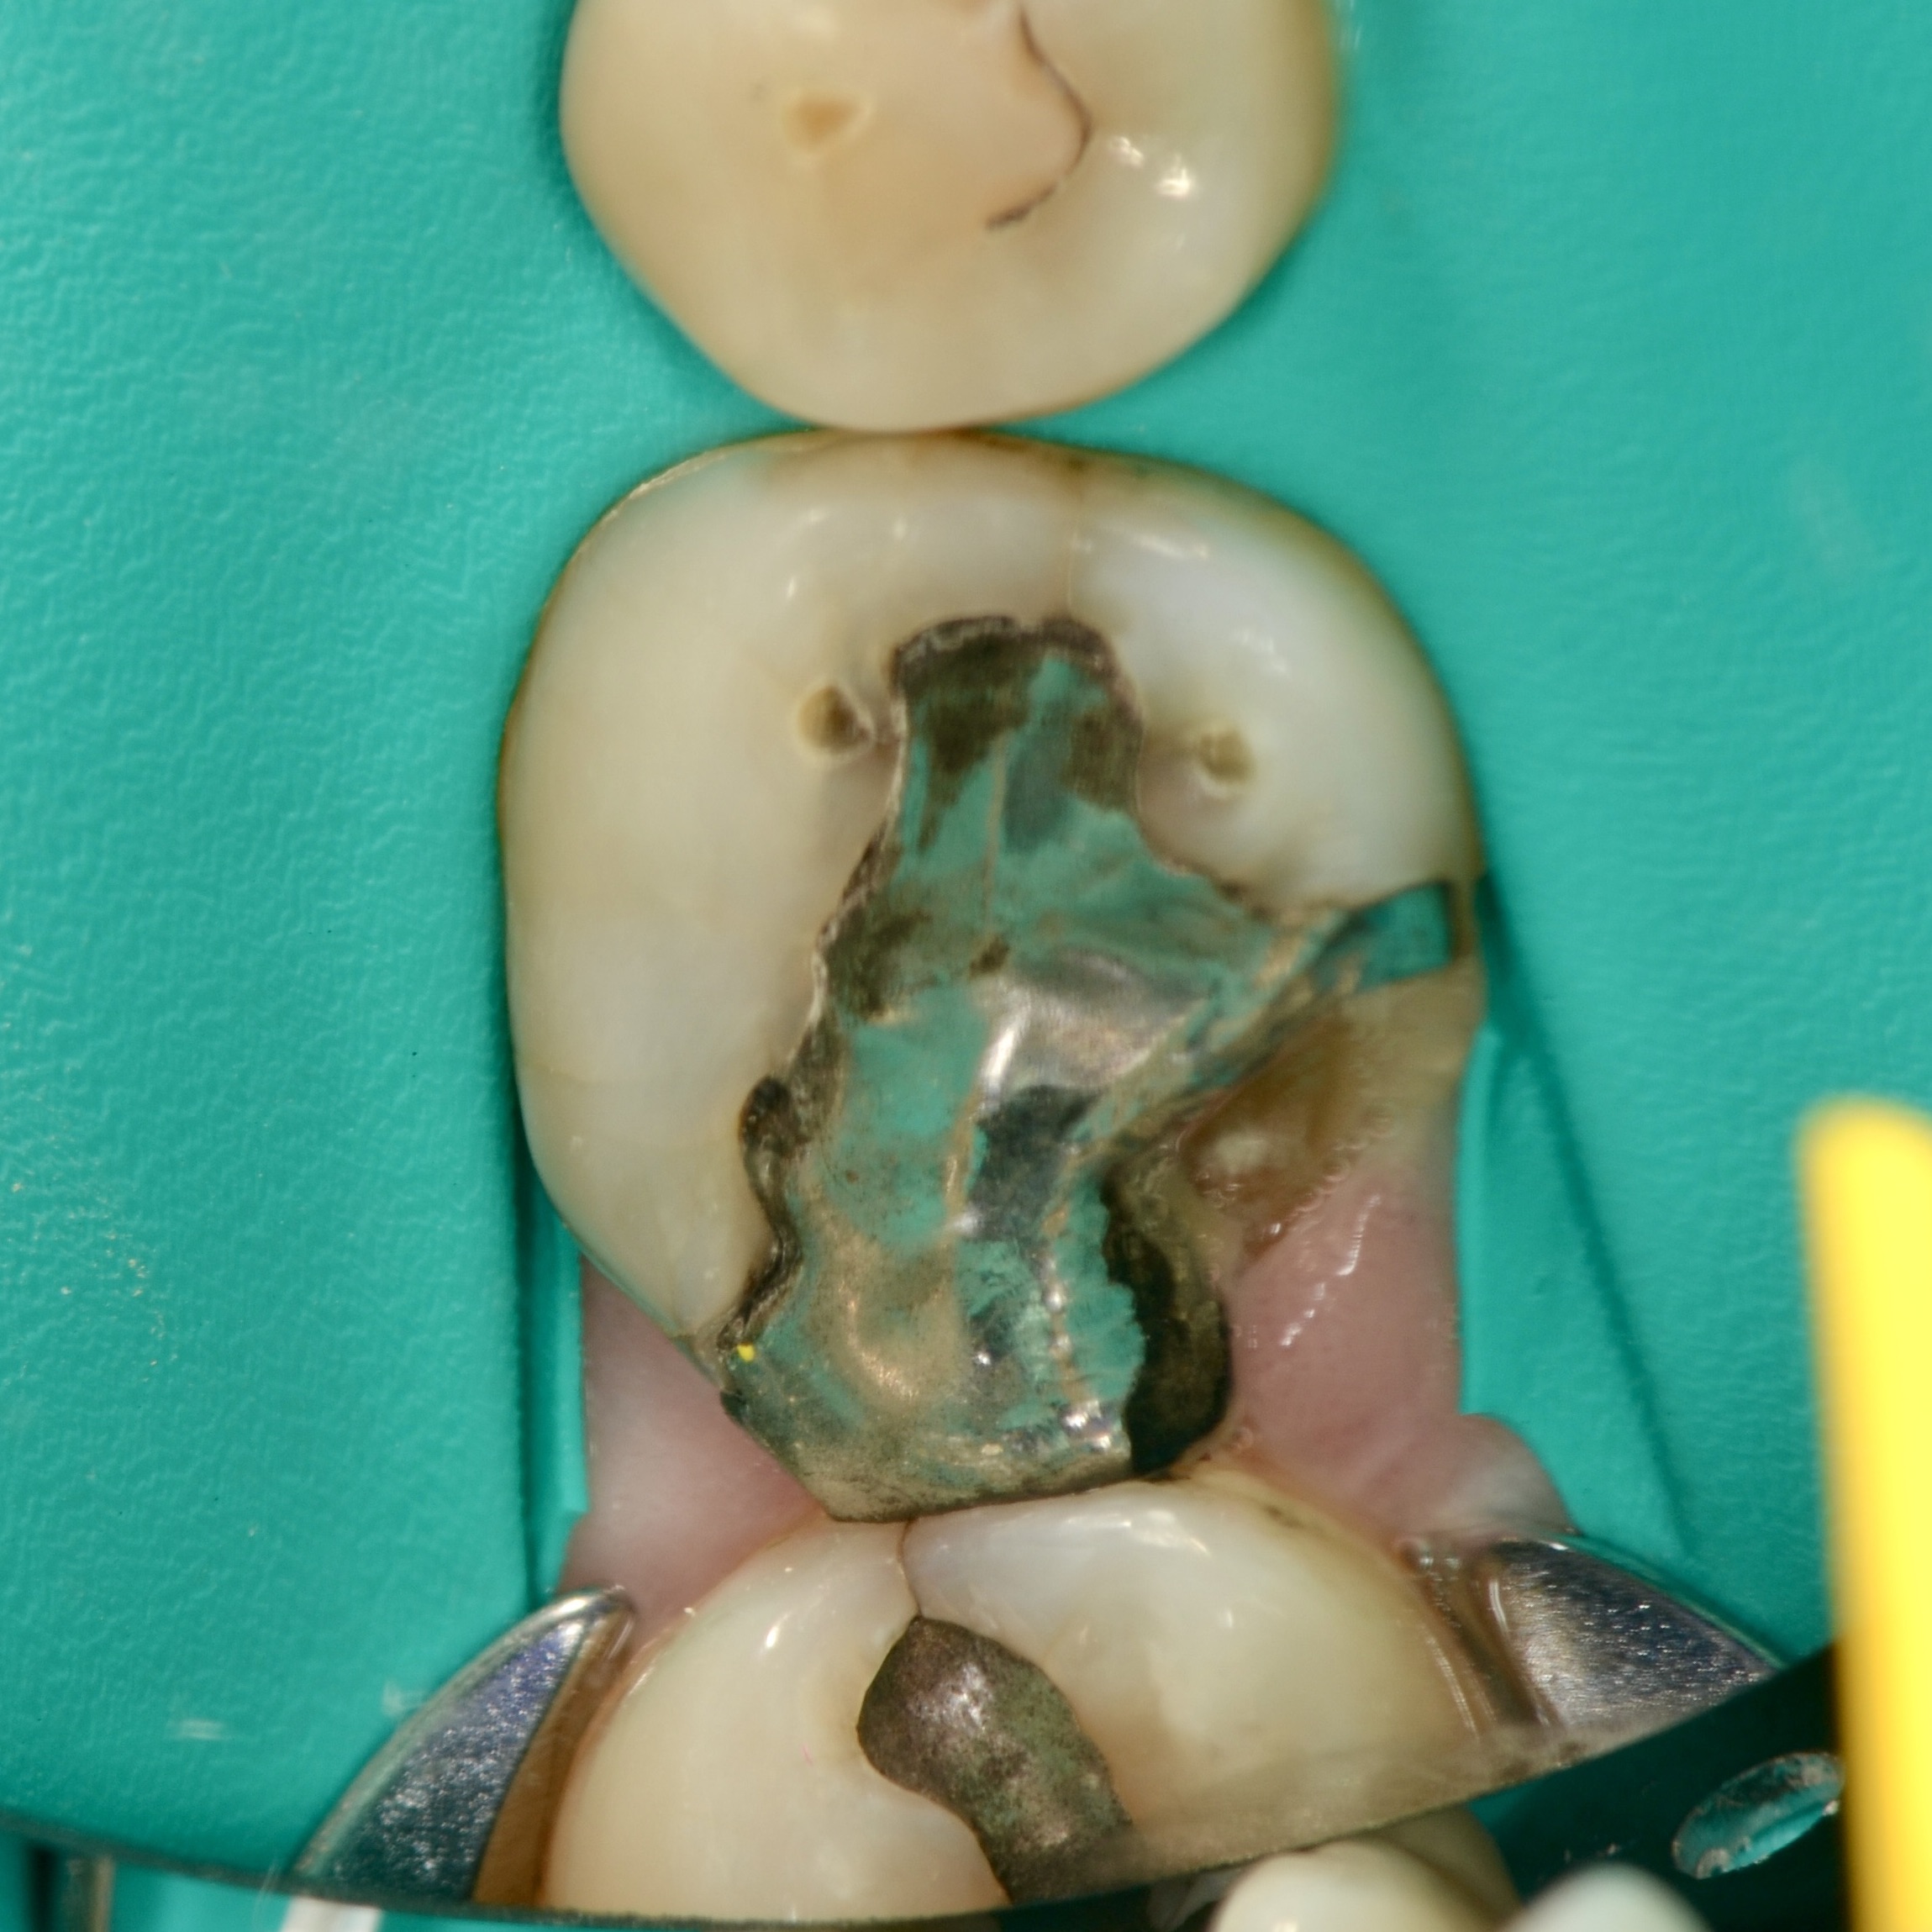

Fractured Tooth and Broken Metal Filling